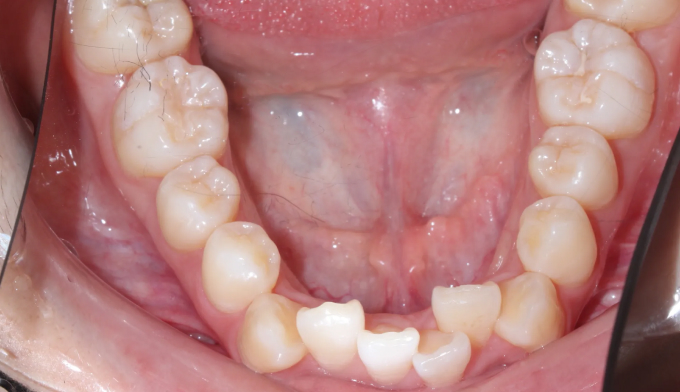

덧니

덧니가 생길정도로 공간이 부족한 경우, 발치교정이 대표적인 방법 중 하나입니다.

하지만 그 필요한 공간의 정도와 안모를 종합적으로 고려하였을때, 비발치로도 충분히 가능한 경우가 많습니다.

이번 케이스도 필요한 공간이 많긴 하지만, 입의 보양이나 각도를 고려하였을 때 비발치로 교정 가능한 경우라 판단되어 발치없이 성공적으로 치아를 배열하였습니다.

총 교정기간은 15개월입니다.